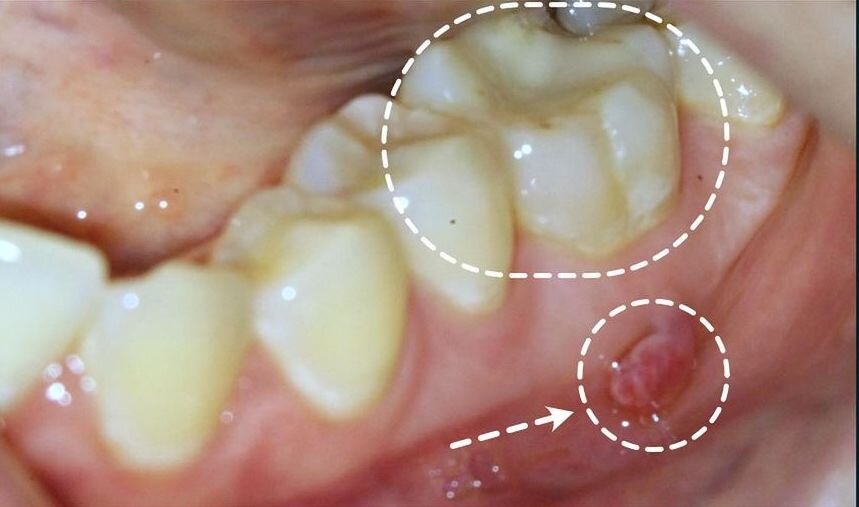

Зуб выглядит абсолютно нормально, но на десне образовался свищ.

Вокруг корней зуба в кости было объемное воспаление (темное пятно на снимке). Иногда в таких случаях образуется свищевой ход, который открывается на десне. Через него дренируется (вытекает) воспалительная жидкость или гной.

А это фото сделано через 2 недели после ювелирного (с микроскопом) и нежного (с надежной анестезией) лечения корневых каналов. Уже в процессе лечения свищ закрылся, что говорит о ранней положительной динамике.